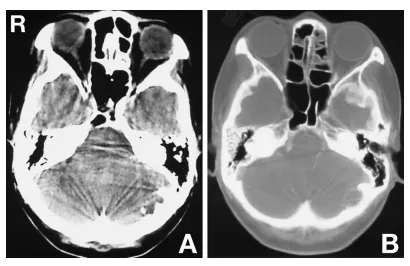

计算机断层扫描(CT)显示左侧后颅窝内板处有一伴钙化的低密度肿块(图2A)。骨窗CT显示颅骨内板受侵蚀(图2B)。

图2A:计算机断层扫描(CT)平扫显示左侧后颅窝内板处一伴钙化的低密度区。B:骨窗CT扫描显示颅骨内板受侵蚀。